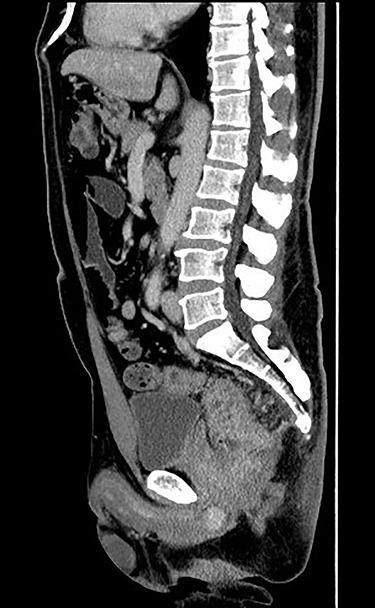

直肠癌和前列腺病变的同步机器人辅助手术。

Simultaneous robot-assisted surgery for rectal cancer and prostatic lesions.

Robotic surgery has become prevalent in many departments all over the world because of its usefulness. It is used in many cases, as well as in gastrointestinal surgery, which treats the rectum as pelvic surgery, urology and gynecology. We experienced two cases of joint surgery, with urology as pelvic surgery. The patient underwent robot-assisted low anterior resection, combined prostate resection and ileostomy for prostate invasion of rectal cancer. He was discharged without any complications. Robotic surgery was considered to be useful in surgery to manipulate the same area. In addition, it was considered that smoother and safer surgical procedure could be possible by conducting preoperative meetings with the participating departments.

摘要

由于其实用性,机器人手术在世界各地的许多科室已变得很普遍。它被用于许多病例,包括胃肠外科(将直肠手术视为盆腔手术)、泌尿外科和妇科。我们经历了两例联合手术,其中泌尿外科手术作为盆腔手术。该患者接受了机器人辅助低位前切除术、联合前列腺切除术以及因直肠癌侵犯前列腺而行的回肠造口术。他出院时没有任何并发症。机器人手术被认为在操作同一区域的手术中很有用。此外,通过与参与科室召开术前会议,认为可以实现更顺畅、更安全的手术过程。